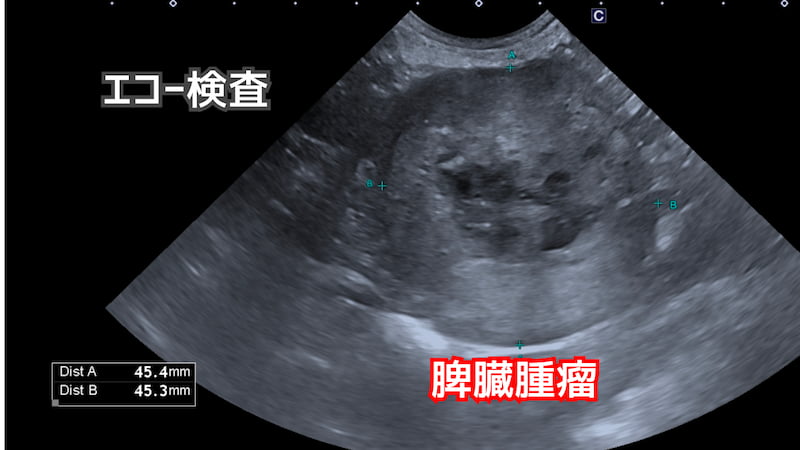

- 超音波(エコー)検査:腫瘤の大きさ・状態・出血の有無・他の臓器との関係を確認

また、以下の写真の通りエコー検査では脾臓から腫瘤が発生していることが分かりました。